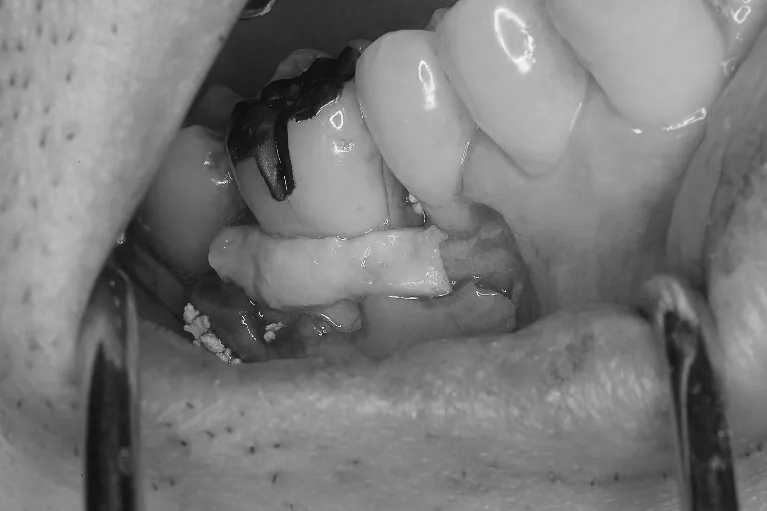

Case2

術前

術中

術後

| 治療説明 | 右下6に重度の歯周病があり、通常の歯周治療でも改善しませんでした。歯周組織再生療法を行い、吸収してしまった骨を再生し、今後の歯周病の進行リスクを減らす事ができました。歯肉退縮もあったため同時に結合組織を移植し、骨と歯肉の再生を同時に行っています。 |

| 治療回数・期間 | 6ヶ月 |

| 副作用とリスク | 手術後に出血、腫脹、疼痛が生じることがあります。手術後は術部の創傷安定のためにブラッシング制限、食事制限があります。手術が複数回となることがあります。 |

| 料金(税込) | 再生療法:165,000円 結合組織移植:55,000円 総額:220,000円 |